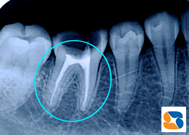

これは、私の歯を横割りにした画像です。左下の奥歯が、丸ではなく、視力検査のCのような形をしていました。自分の歯の輪郭を鮮明に知ることができて感動です。